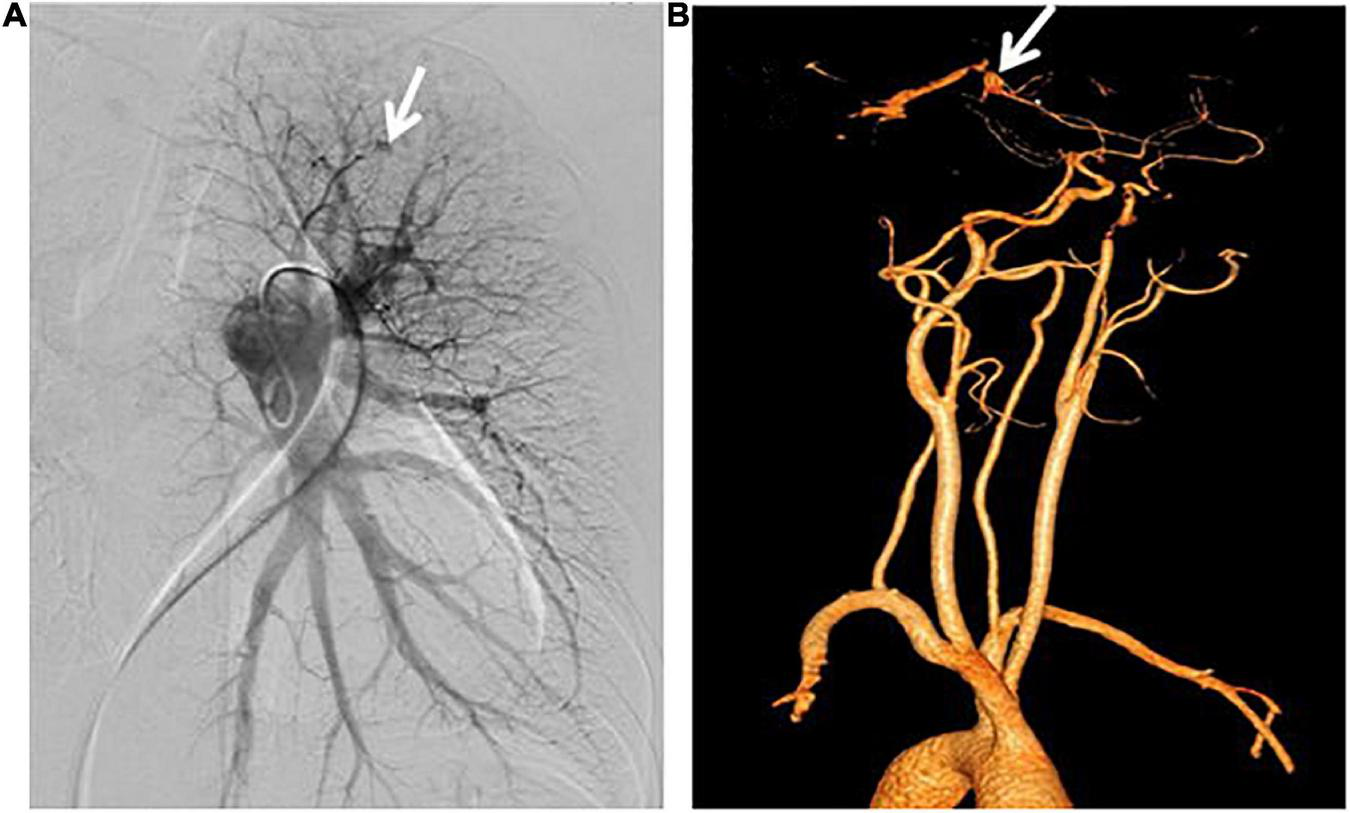

The result of right heart contrast echocardiography was consistent with pulmonary arteriovenous malformations (AVMs). The result of echocardiography was indicative of pulmonary hypertension (PH). Electronic gastroscopy showed chronic non-atrophic gastritis but no gastric vascular malformations. Pulmonary function showed mild diffusion dysfunction. No obvious filling defect or vascular malformations were observed on CTPA (Figure 2A), but several ground-glass opacities were seen on the lung window of CTPA, where one of 7.8 mm × 7.5 mm in diameter was located in the right upper lung lobes (Figure 2B). The result of right heart catheterization (RHC) is shown in Table 2. Pulmonary angiography showed AVMs of the left upper pulmonary artery (Figure 3A), and anterior cerebral artery malformation was seen in cranial computed tomographic angiogram (Figure 3B). Genetic testing revealed the patient carried heterozygous variants in the ENG c.1195-1196del p.Arg399GlyfsTer2. Except her son, all her three daughters carried a heterozygous variant at the ENG c.1195-1196del locus.

Figure 3. Pulmonary angiography and cranial computed tomographic angiogram. (A) Arteriovenous malformations of the left upper pulmonary artery were shown. (B) Anterior cerebral artery malformations were revealed.